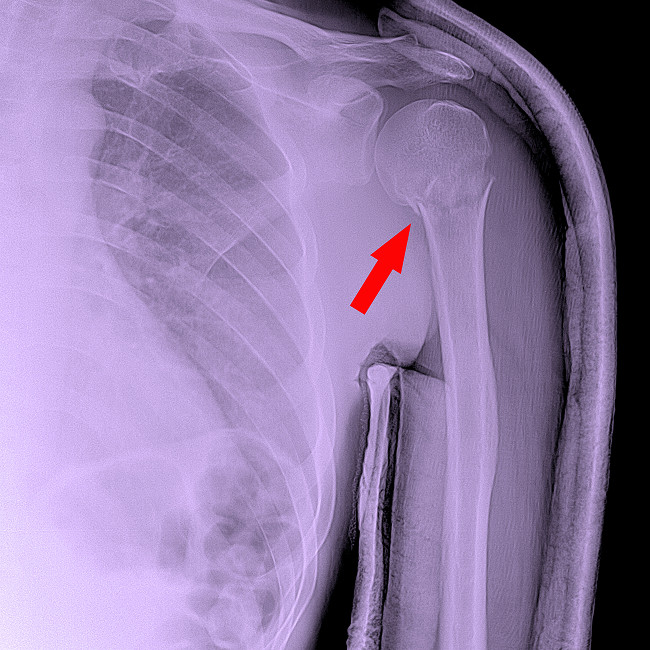

Диафизарные переломы

Диафизарные переломы – это повреждения тела кости, возникающие при прямом ударе или падении. Такие травмы часто сопровождаются выраженным смещением, и без оперативного вмешательства восстановить правильную ось сложно.

В некоторых случаях применяют консервативный метод – иммобилизация гипсом на плечо или съемной повязкой, но при множественных отломках предпочтительнее операция с установкой пластины. Фиксация позволяет пациенту раньше начать движения и сокращает срок реабилитации.